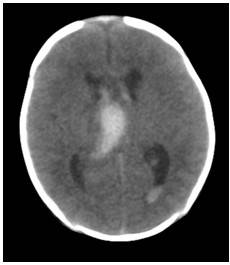

En contraste con los hallazgos de la RM se decidió realizar tomografía computadorizada para corroborar el diagnóstico. (Figura 3).